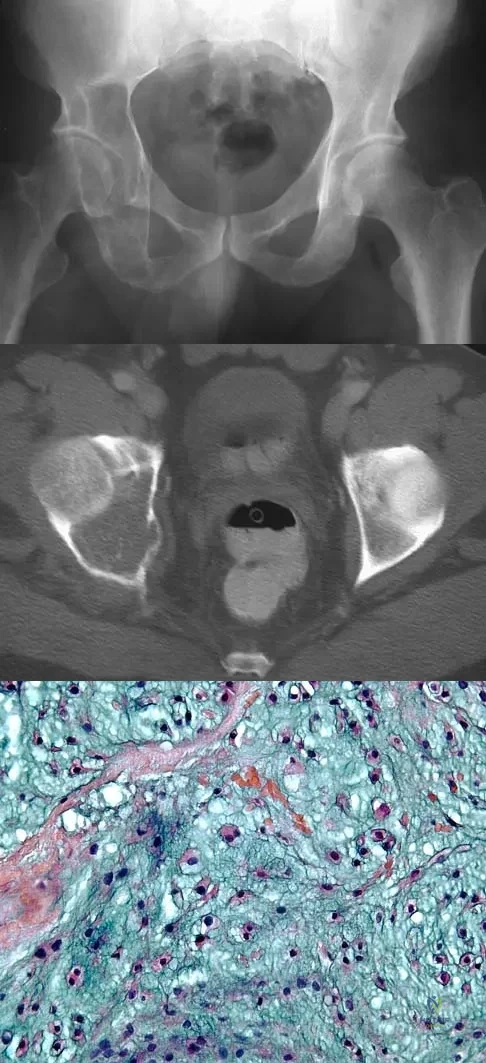

A 10-year-old girl reports activity-related bilateral arm pain. Examination reveals no soft-tissue masses in either arm, and she has full painless range of motion in both shoulders and elbows. The radiograph and bone scan are shown in Figures 20a and 20b, and biopsy specimens are shown in Figures 20c and 20d. What is the most likely diagnosis?

Explanation

A 15-year-old boy has had pain in the right shoulder for the past 3 months. He denies any history of trauma and has no constitutional symptoms. Examination reveals a large firm mass in the proximal arm. A radiograph and MRI scan are shown in Figures 27a and 27b. Biopsy specimens are shown in Figures 27c and 27d. Management should consist of

Explanation